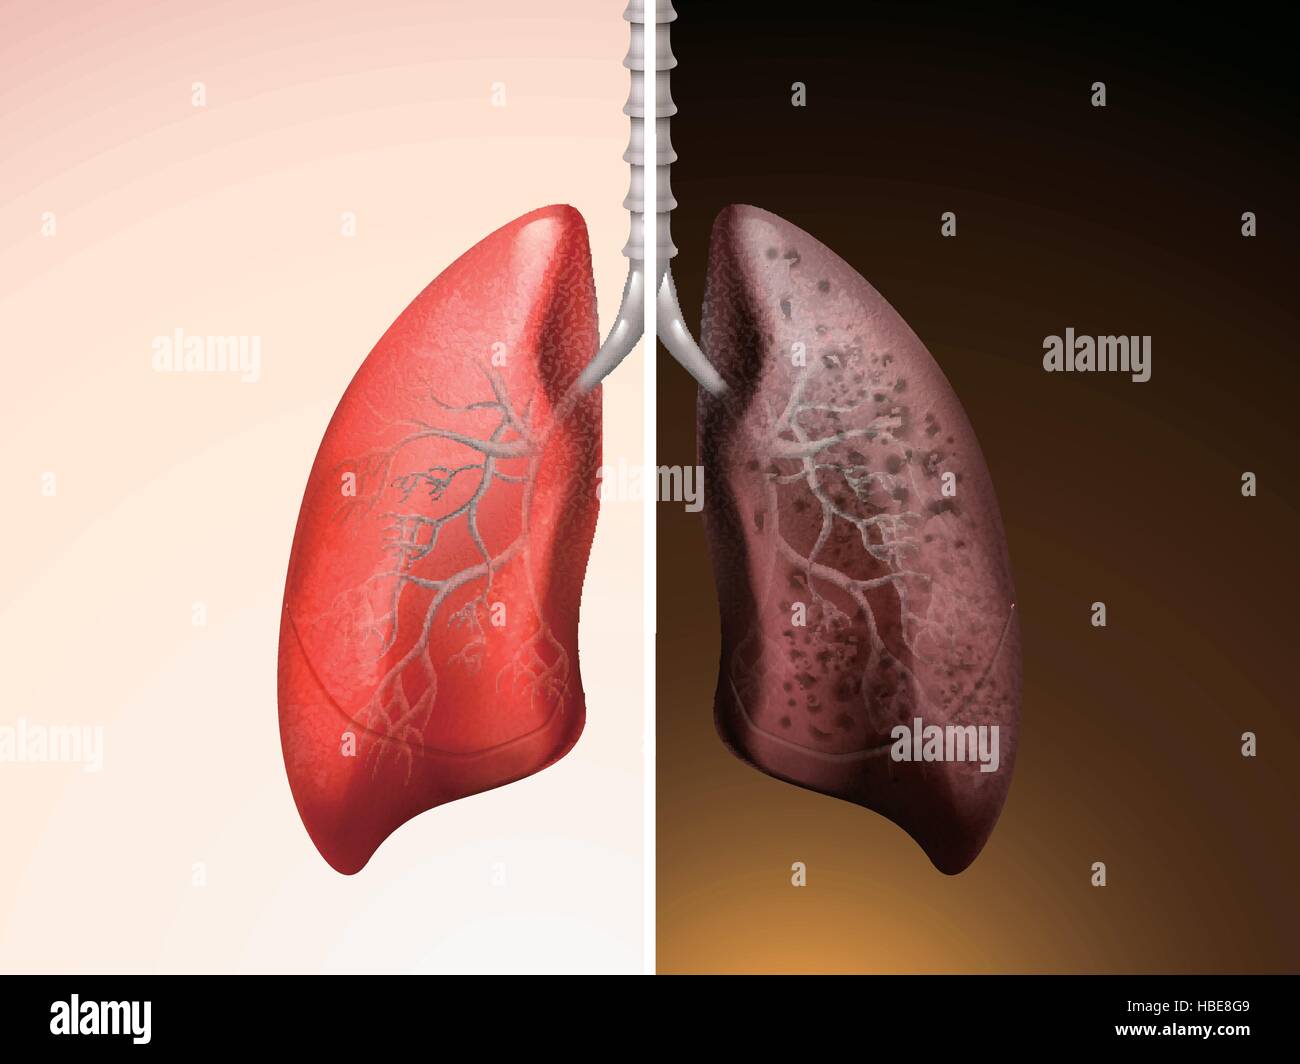

Здоровые Легкие Картинки

Здоровые Легкие Картинки 117 фото